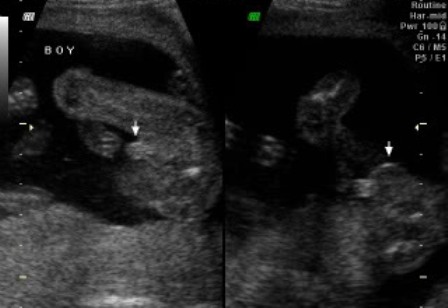

Krisztike! Nekünk fiúnk lesz és ahogy látom fiús a pocakom. De hallottam már ezt cáfolni is.

Rólunk! Voltunk a szúrás utáni kontroll UH-n, ami felért egy genetikai UH-nak, annyi mindent mértek, néztek meg. A gyerkőc, persze egyből széttárt lábakkal várt minket. Újabb megerősítés a fiúra. Méretei, szervei rendben.

A doki még azt is megmondta, hogy szépen lelapul a füle a fejére, nem fog elállni